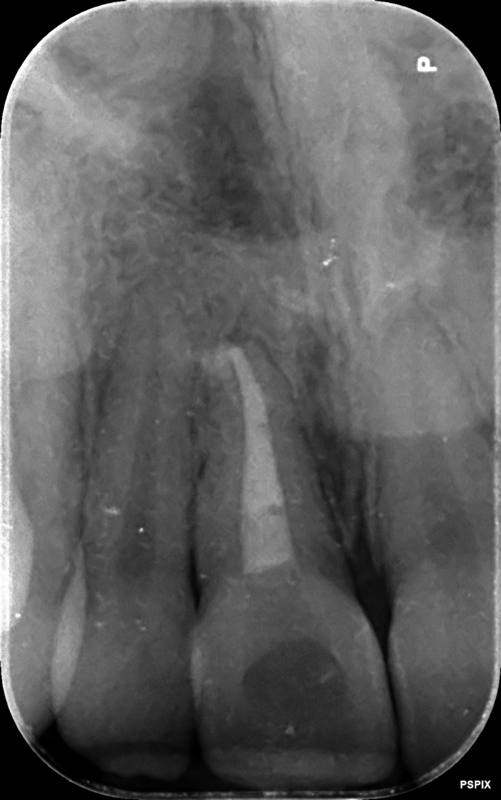

Case 5 – Dental Trauma

Severe Intrusion during braces